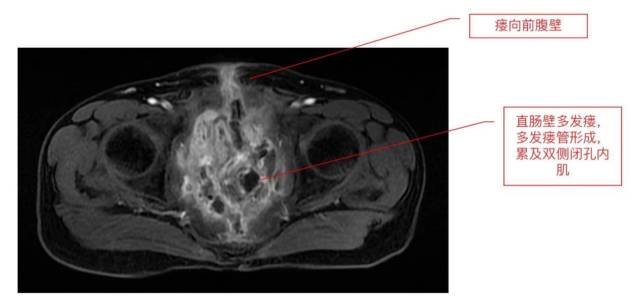

因病情复杂、病程长,有六次盆腔手术史及放射治疗史,董先生出现了直肠吻合口-盆腔小肠-尿道残端-腹壁-阴茎复杂瘘。腹部疼痛和瘙痒、反复感染发热、进食困难等问题困扰着他,更让他痛苦的是,他的体表4个出口持续性排出消化液和粪渣,日常护理非常困难。巨大的身心负担令他近乎抑郁,畏惧进食,出现重度营养不良。

经充分术前准备后,马腾辉团队为董先生进行了剖腹探查手术,术中探查发现盆腔肠管多发粘连,伴回肠-结肠-皮肤-阴茎-盆腔-代直肠吻合口瘘并多发瘘管。手术完整切除了盆腔放射性损伤严重的病变小肠、病变代直肠吻合口,并清除盆腔脓肿。随后将直肠远端封闭,自体大网膜内移植填塞于盆腔间隙,进行全盆底重建修复,在为患者解除病痛的同时,尽量减少再次复发的风险。手术历时5个小时,出血仅约300ml。